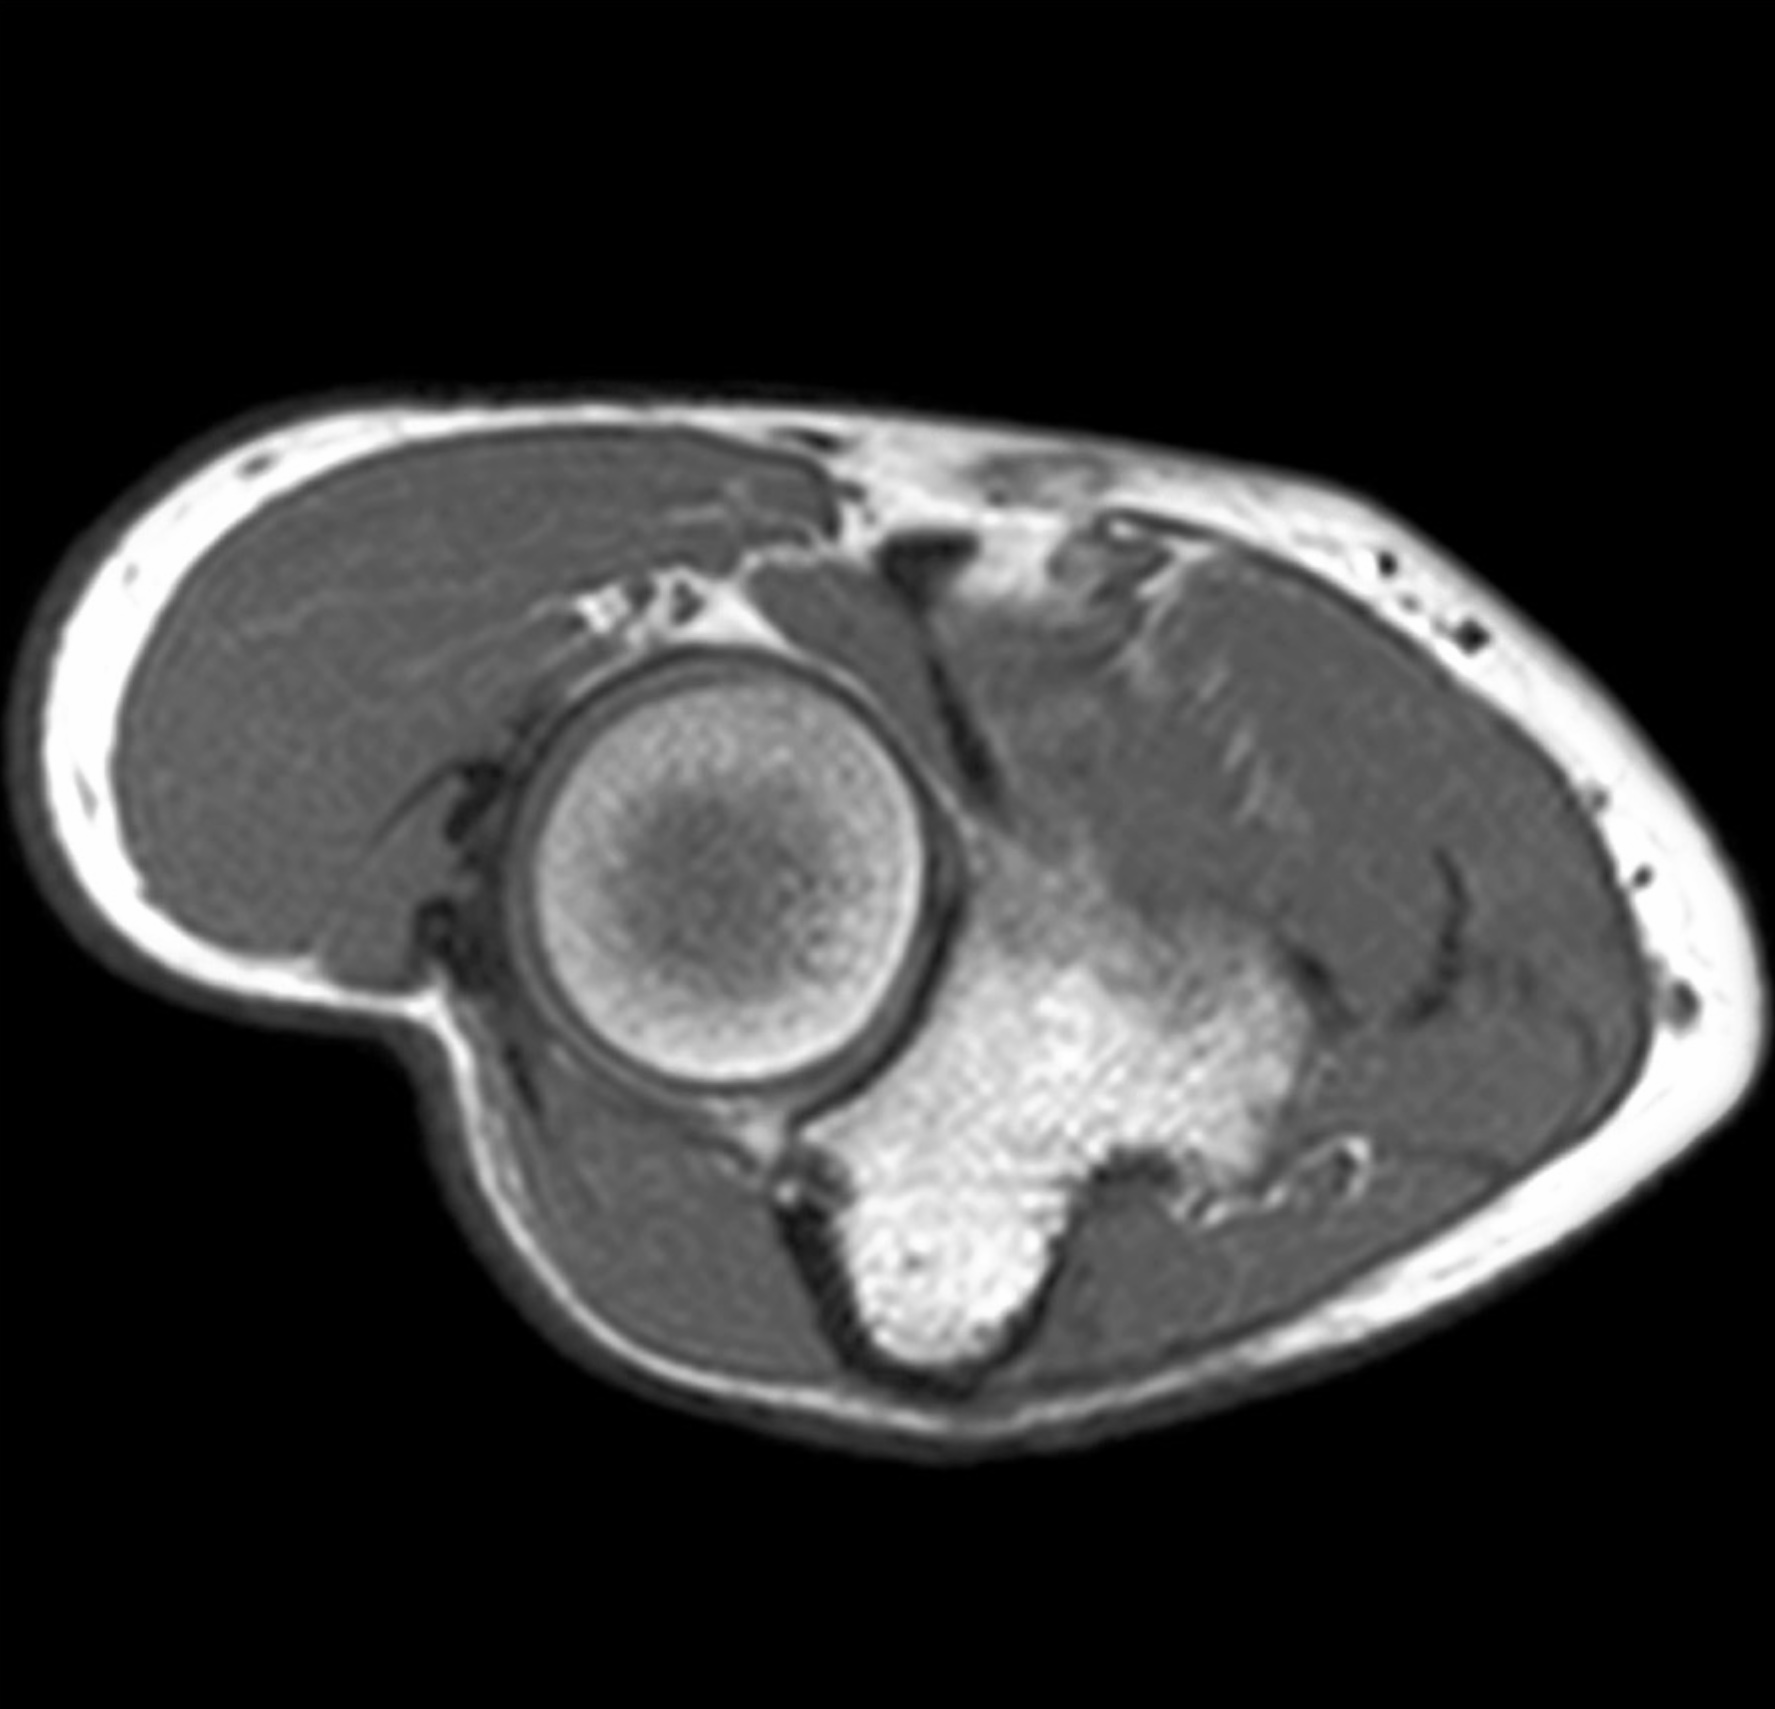

1. The biceps brachii muscle is the most powerful supinator. Discuss the anatomy of the anterior compartment of the arm, including boundaries, contents, musculature, vascular supply, innervation, lymphatics and relationships.

2. A 27-year old patient suffers a humeral shaft fracture at the radial groove. Discuss the anatomy of the posterior compartment of the arm, including boundaries, contents, musculature, vascular supply, innervation, lymphatics and relationships. Differentiate between motor deficits of posterior arm and posterior forearm musculature relative to branching of the radial nerve superior and inferior to the radial groove.